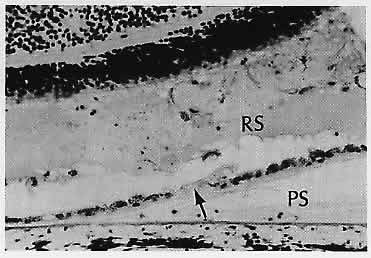

CENTRAL SEROUS CHOROIDOPATHY (Figs. 17 AND 18)

Fig. 17. Schematic diagram correlates the histologic changes on the left (A, B and C) with (a) the fundus changes, (b) the very early fluorescein stage, and (c) the late fluorescein stage. A. Simple small detachment of the retinal pigment epithelium (RPE). (NR, neural retina) B. Simple large detachment of the RPE. C. Small detachment of the RPE with overlying serous detachment of the neural retina (i.e., idiopathic central serous choroidopathy).

Fig. 18. Eosinophilic fluid is present in the subretinal pigment epithelial (RPE) space (PS) and in the subsensory retinal space (RS). Fluid presumably goes from the sub-RPE space into the subsensory retinal space through a break in the RPE (arrow).

Central serous choroidopathy (or central serous retinopathy, pigment epitheliopathy, or chorioretinopathy) is an idiopathic disorder usually occurring in young men. One of more leaks in the retinal pigment epithelium allow fluid from the choriocapillaris to collect in the potential space beneath the sensory retina. The result is a blister-like sensory retinal detachment with clinical metamorphopsia. On fluorescein angiography, the leakage point classically appears as a “smokestack” as the fluorescein enters the subretinal space through the leakage site. The borders of the detachment are fuzzy. In contrast, any accompanying retinal pigment epithelial detachment has sharp margins. The condition can recur, and the cause is not understood.94

A number of conditions can cause secondary retinal pigment epithelial leakage with retinal pigment epithelial and sensory retinal detachments, including scleritis, inflammation or tumors of the choroid (e.g., nevus and hemangioma),95 and subretinal neovascularization.96